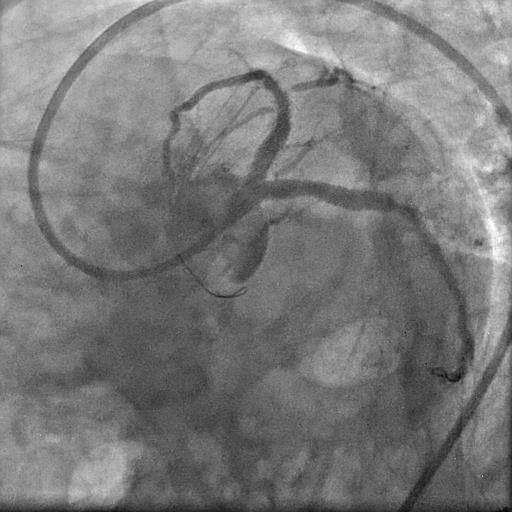

Picture 4: Check angiogram demonstrating thrombus embolisation.

The patient was urgently transferred back to the catheterisation laboratory for revascularisation. A check angiogram prompted reconsideration of the initial strategy (rotational atherectomy vs cutting balloon), as distal thrombus embolisation was noted.